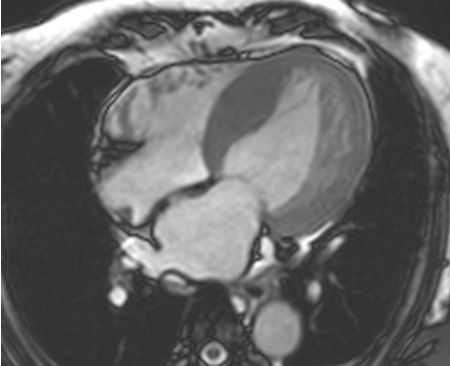

Ressonância nuclear magnética cardíaca (RNMC) de paciente com infiltração amiloide cardíaca. Após injeção de contraste de gadolínio, na fase tardia há um anel basal subendocárdico no ventrículo esquerdo (corte de 4 câmaras)

Do acervo de Dr Jessica Webb; usado com permissão